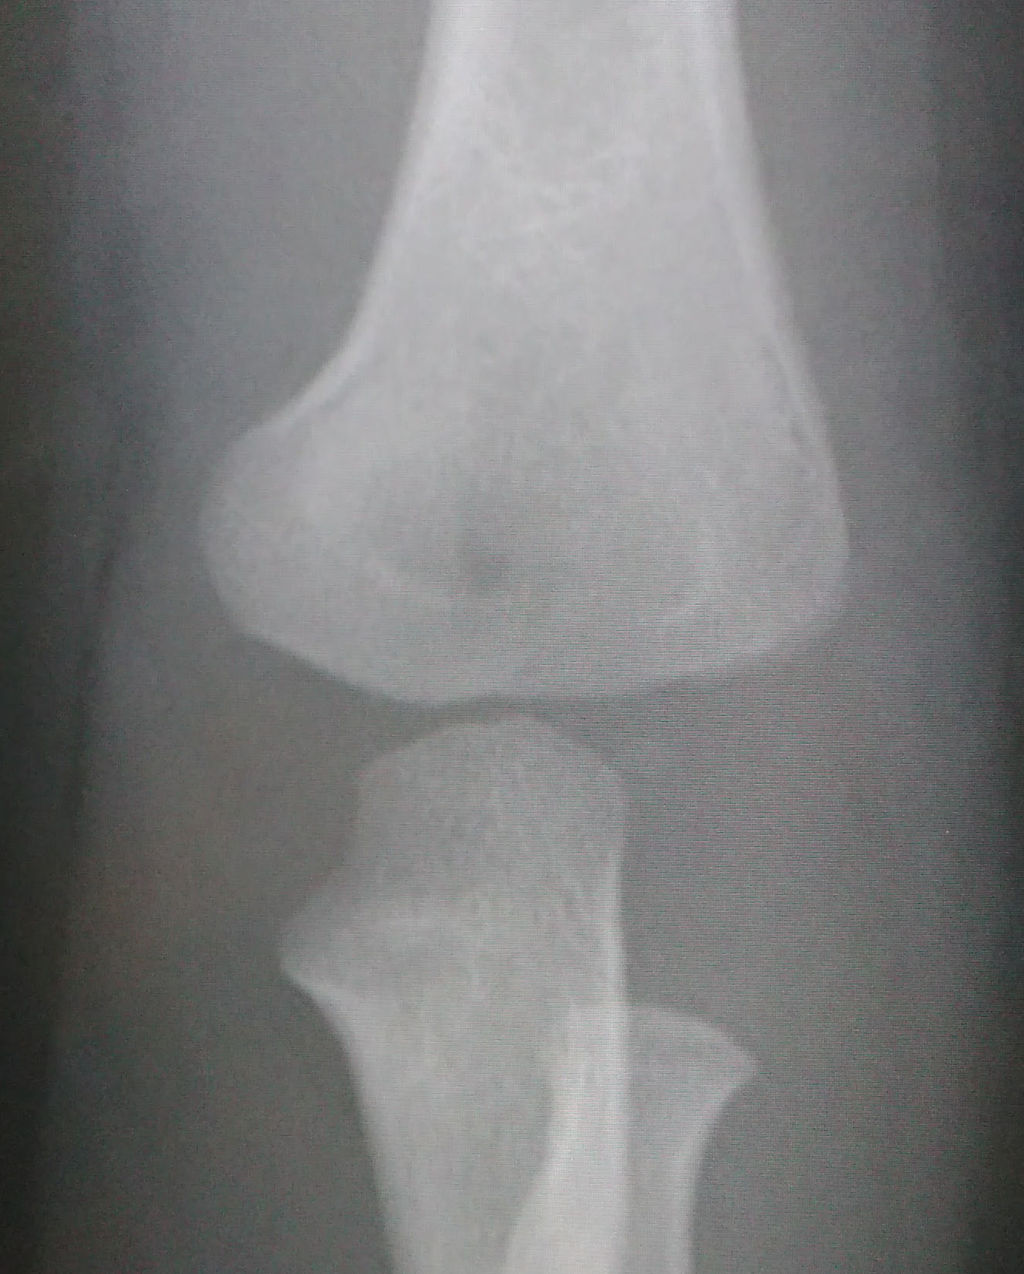

豊富な図や画像が提示されているため、ほとんどの骨折や脱臼に対応することが可能です